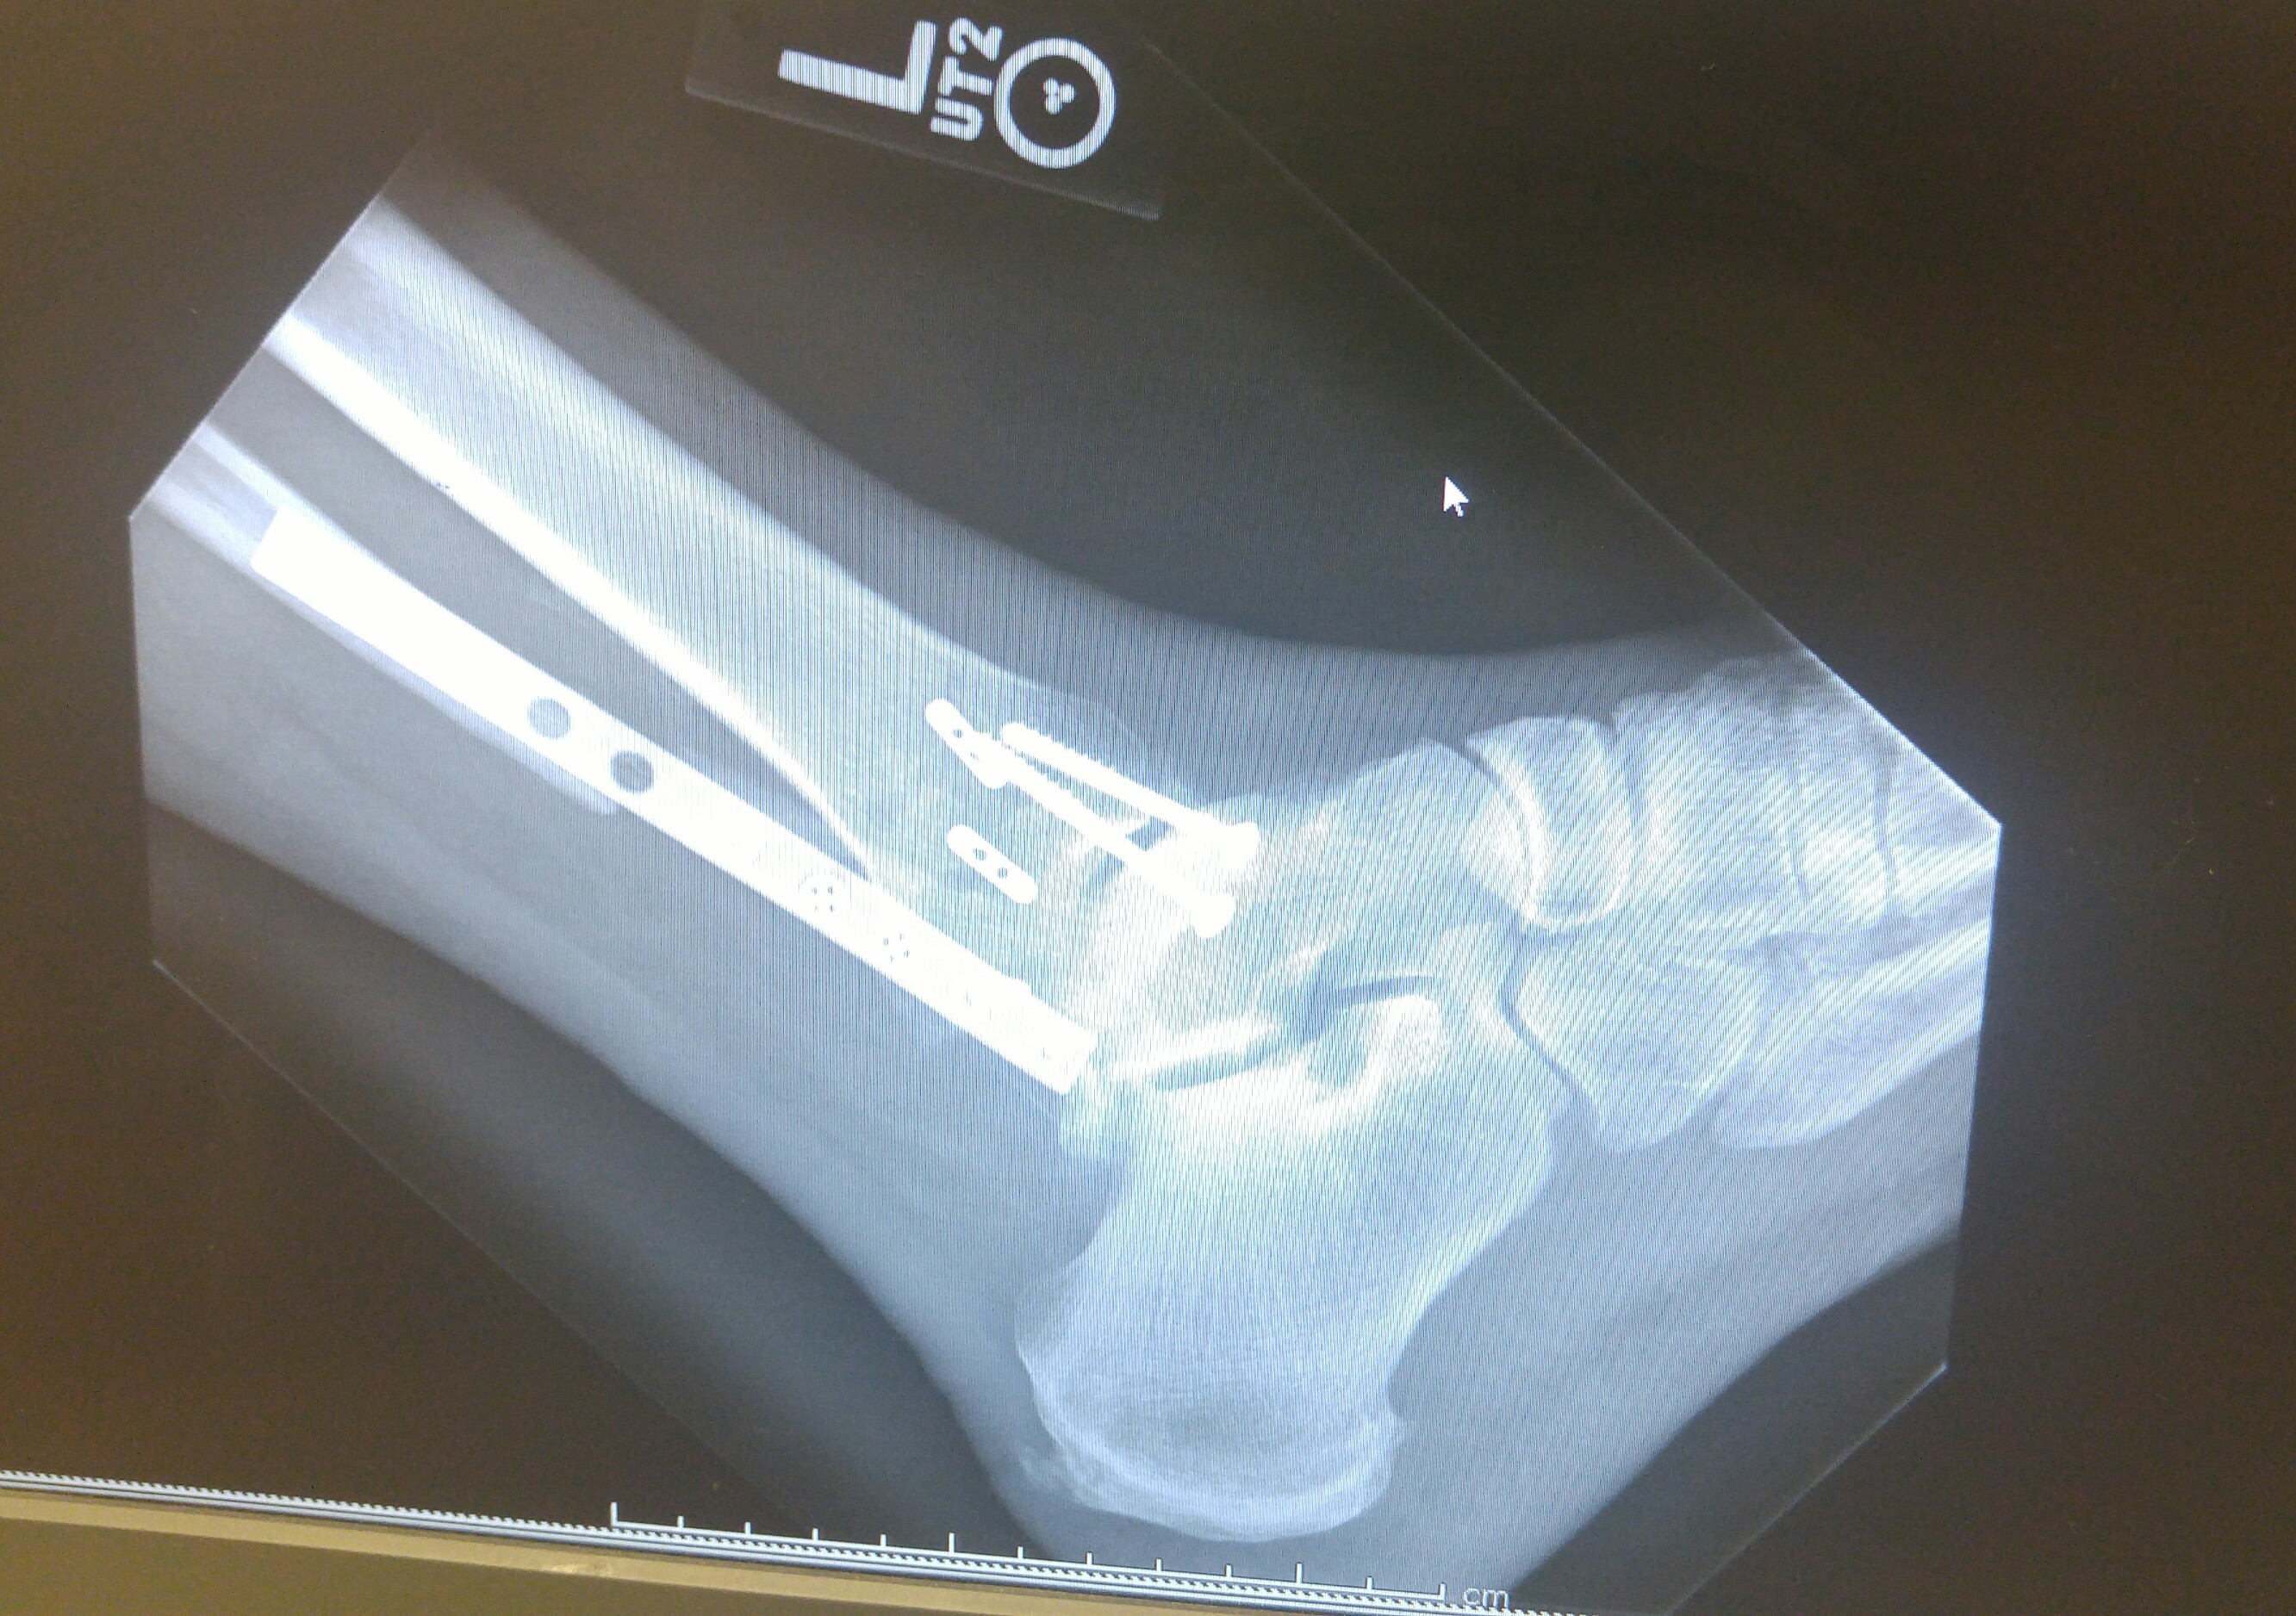

Broke my able and tore the ligament that hold the fibula and tibia in place. Did it on May 13 and here are my x-rays that were taken yesterday. Be as compliant as you can so you don't have to join the hardware club.

Due to the remaining gap in the fibula, it will be at least another 2 weeks before I can start putting any weight on it.

Thankfully, no. Just lots of screws, a plate and some heavy duty thread to secure the two bones in place until the ligaments heal. If you zoom in and look close at the bottom of my tibia and fibula, you will see two light grey horizontal lines. Those are the tunnels drilled and ran the sutures through to tie the two bones together. This technique is supposed to allow for more natural range of motion down the road.The Annoyed Man wrote:Holy cow! Did they actually fuse the ankle?mojo84 wrote:Glad you've been able to avoid surgery do far. Will pray your able heals on its own.

I shared the xrays just to encourage you to be compliant with the doc's instructions. If you do, your chances of avoiding surgery will increase. I had no choice about surgery. Hopefully you will be able to avoid the surgery.